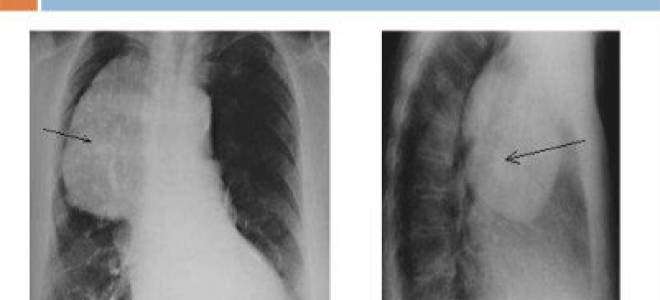

Виды злокачественных опухолей средостения – причины и симптомы рака средостения

Виды злокачественных опухолей средостения – причины и симптомы рака средостения Лечение опухолей средостения Средостение — область грудной полости между легкими,...